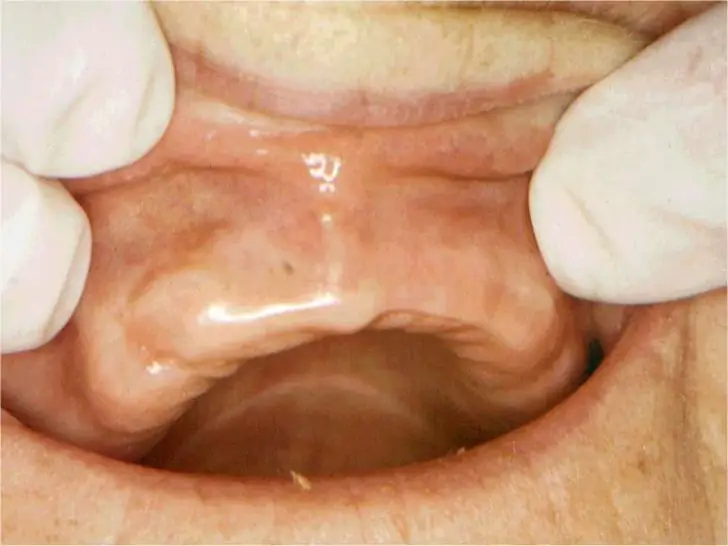

Reservoir Dentures

Prosthodontic Considerations

- If a mouth is dry. Retention of the denture – affected + increased potential for soreness

- Presence of thick saliva may create a problem for maxillary complete denture retention, – create hydrostatic pressure in the area anterior to the post palatal seal area – downward dislodging force exerted upon the denture base

- In an effort to alleviate this problem, a cupids bow can be scribed on the master cast

- According to Watt and Macgregor, extension of the posterior palatal seal line will contain the thick mucous in the posterior part of the denture to provide a seal even if the posterior portion of the denture base is slightly out of contact with the palatal tissues.